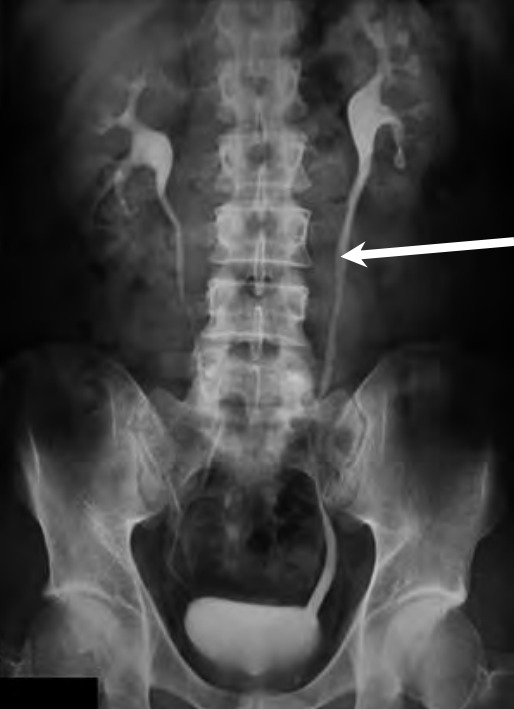

Na prawidłowo przedstawionym radiogramie badania kontrastowego strzałką zaznaczono

A. moczowód prawy.

B. mięsień lędźwiowy prawy.

C. moczowód lewy.

D. mięsień lędźwiowy lewy.